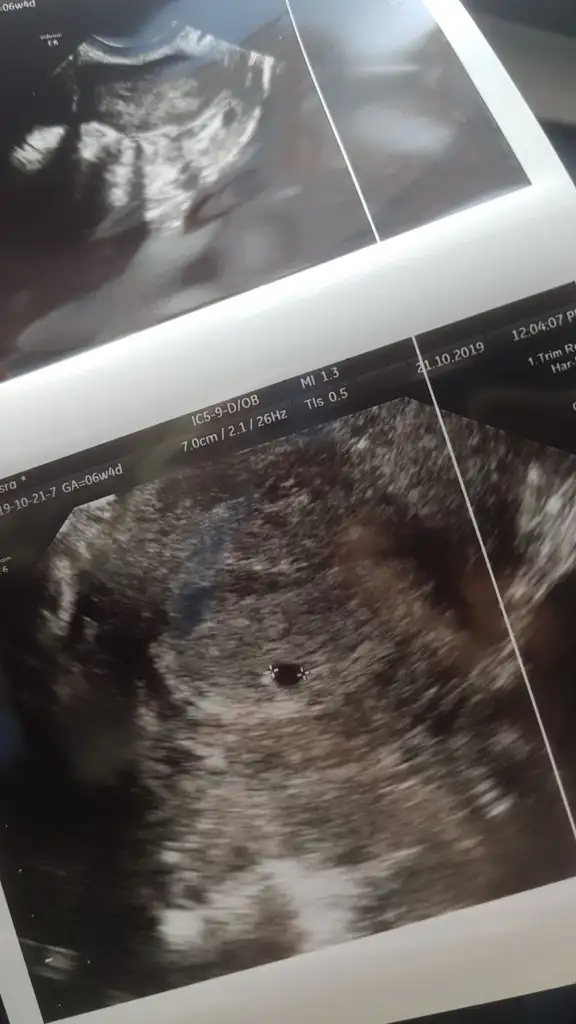

Ben geçen cumartesi öğrendim hamile olduğumu ve rüyamda gördüm eşime test yapip veriyordum ben bakamam diyodum o da bana bakıp gülüyo ve hadi hastaneye gidelim diyodu ertesi gün test yaptım ve sonuç görseldedirrr